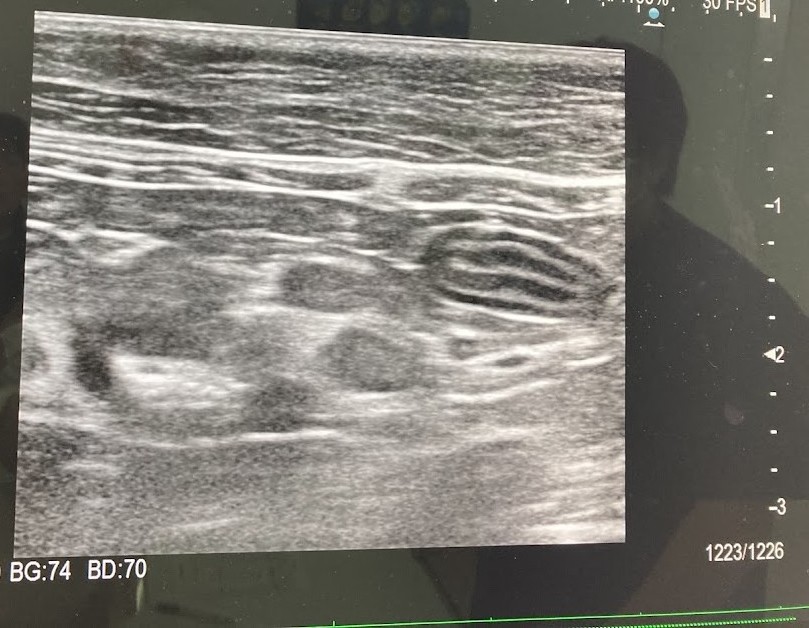

それよりも獣医さんが気にしていたのは、エコー検査。

「小腸は通常五層になってるのですが、途中で断絶している。つまりリンパ節が腫れている様子」

「肝臓に白い点々がたくさんあるようで、結節やガンかもしれない」

・エコー検査をしたら小腸の五層構造が乱れていた